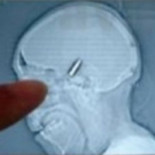

Un portero aficionado bosnio juega un partido entero con una bala en el cráneo

Un portero bosnio de una liga de aficionados de Sarajevo disputó un partido completo sin percatarse de que tenía una bala alojada en su cabeza. Dusko Krtalica, de 51 años, tuvo que ser trasladado al hospital inmediatamente después del encuentro. Al parecer, la bala provino de unos disparos efectuados durante la celebración de una boda cercana. El hombre no se dio cuenta de haber recibido el impacto y siguió jugando.